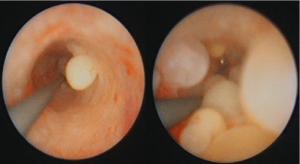

Fall 14: endoskopischer Befund der Harnleiterschleimhaut (URS) bei einem Patienten mit Nephrolithiasis und Koliken aufgrund eines Harnleitersteins.

Welche Krankheit ist zu erkennen? Welche Risikofaktoren prädisponieren für diese Erkrankung? Welche weitere Therapie ist sinnvoll?